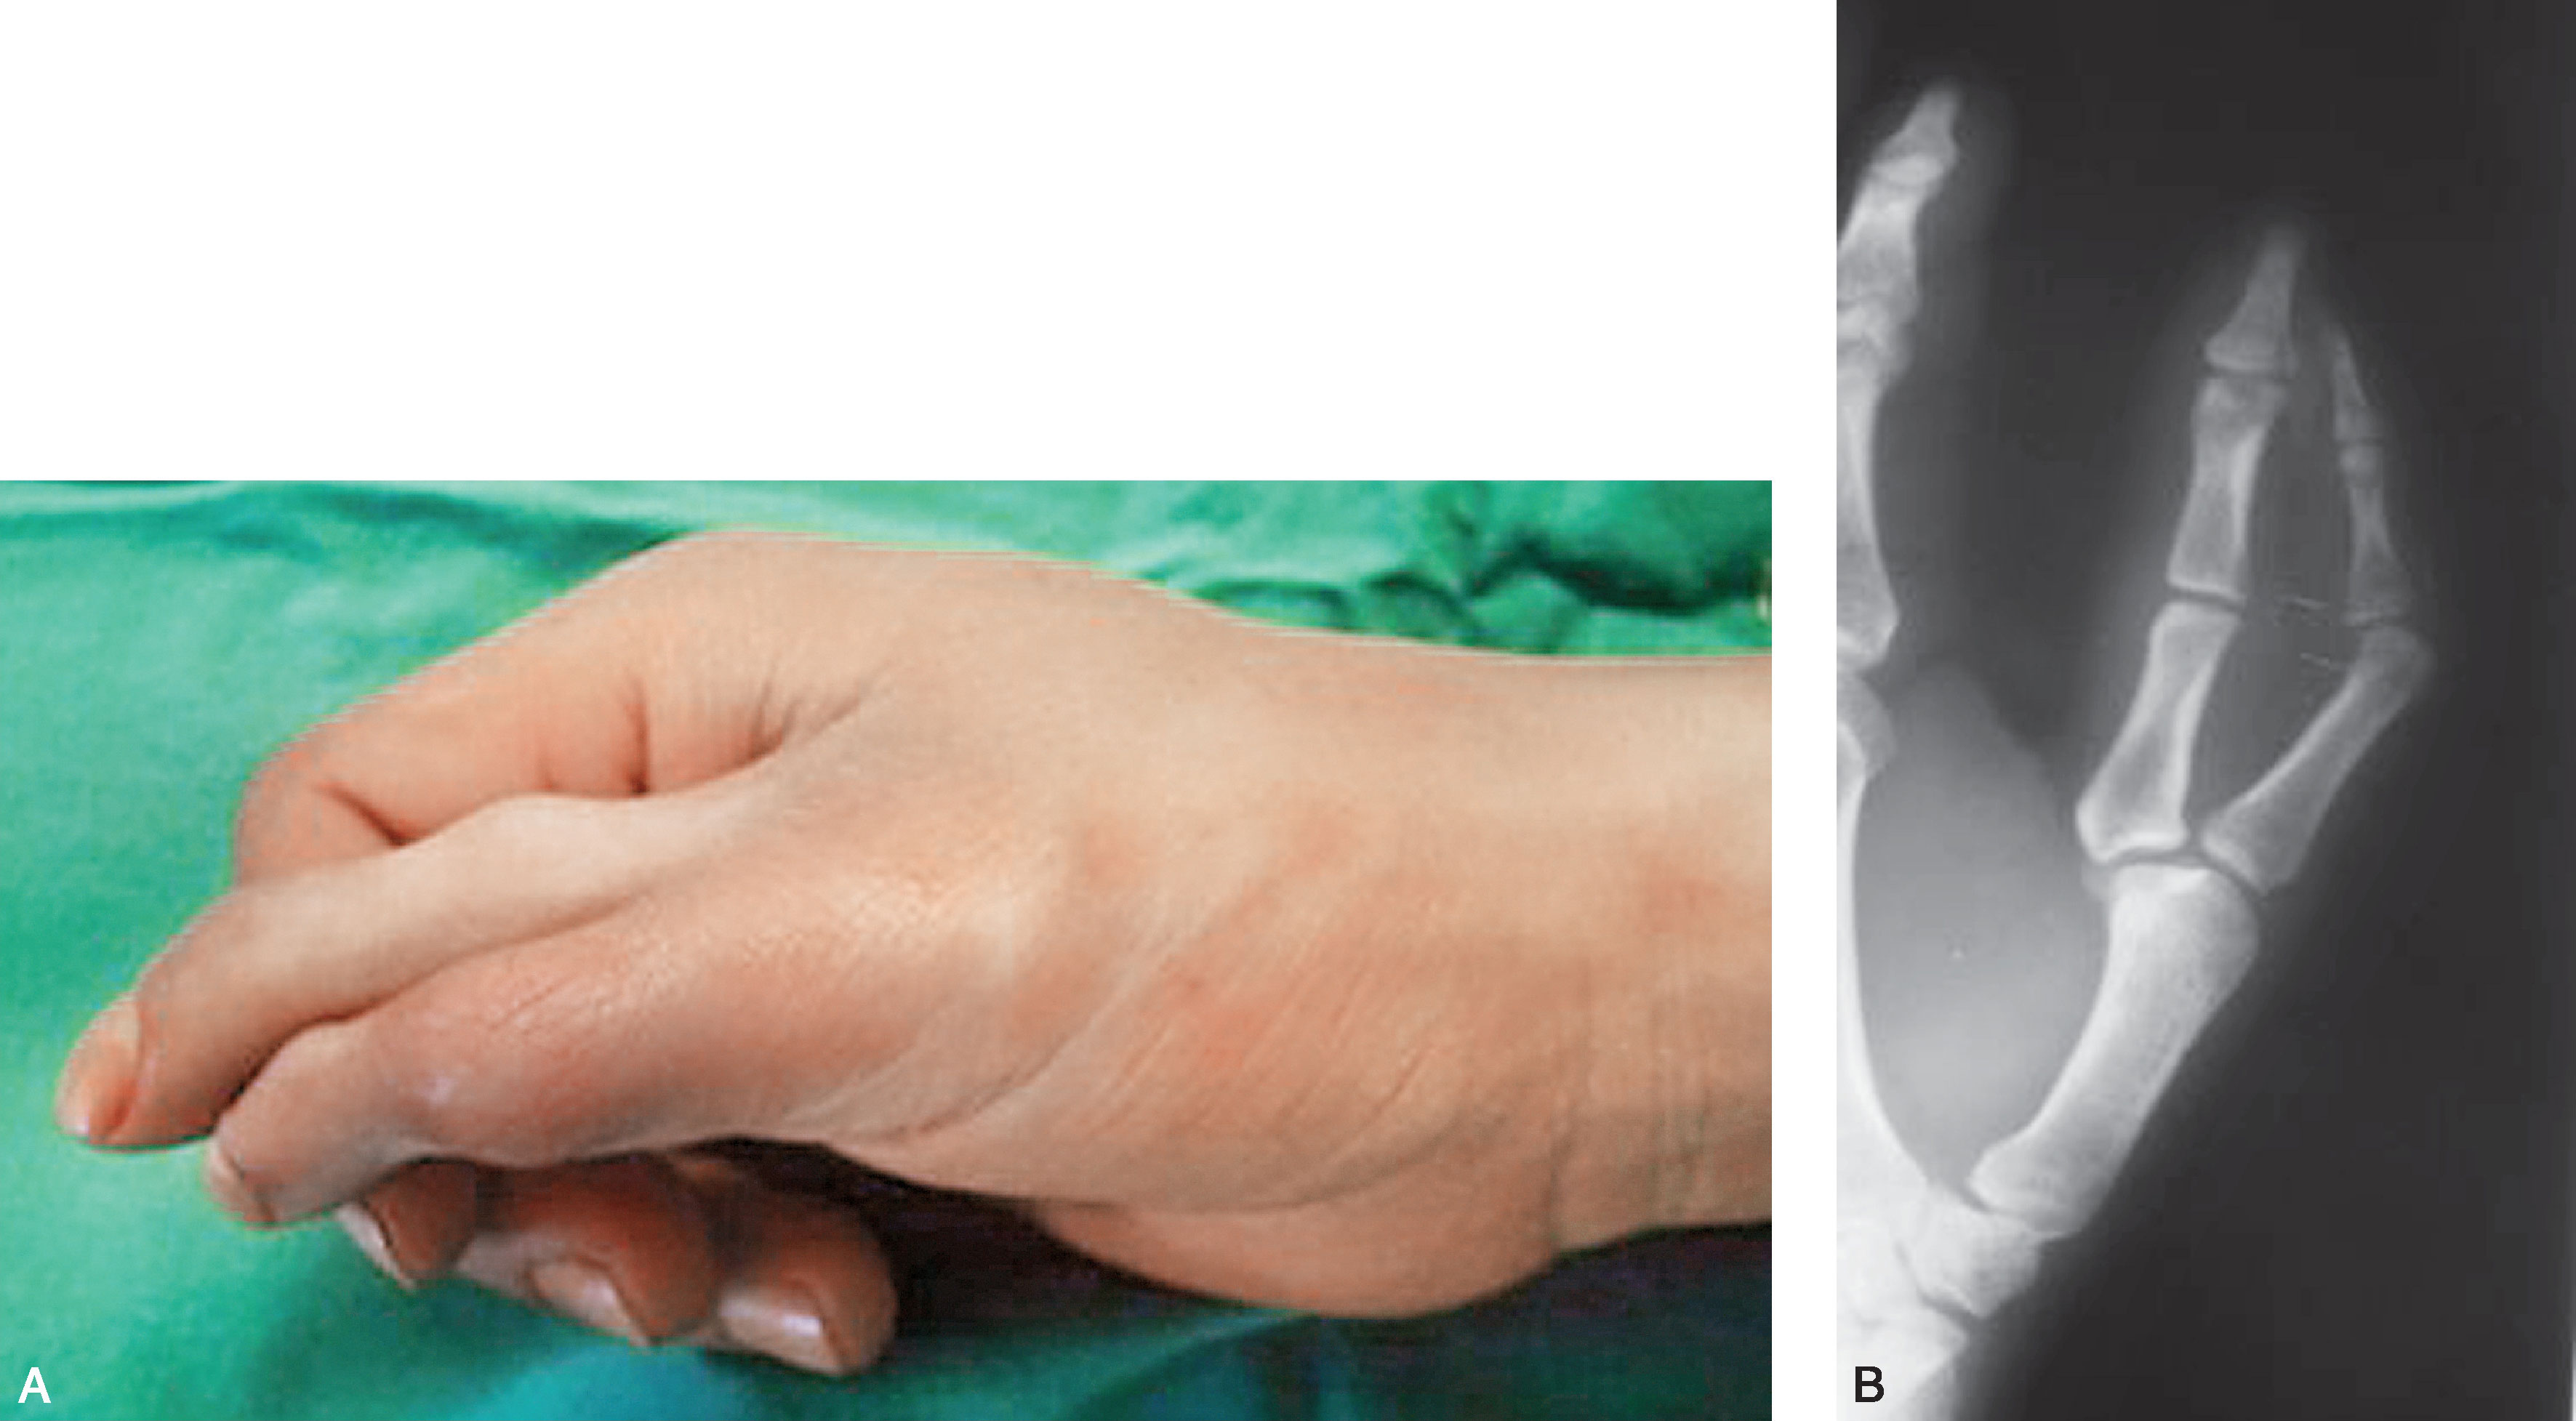

图2-1-46 Ⅶ型病例1

A.右侧多拇指,桡侧拇指发育明显差;B.X 线片显示桡侧拇指为三节细小的指骨,尺侧拇指骨关节结构发育良好,应选择切除桡侧拇指,切除桡侧拇指后,除重建拇短展肌外,尚需行第一掌骨远端桡侧楔形闭合截骨,纠正掌骨力线